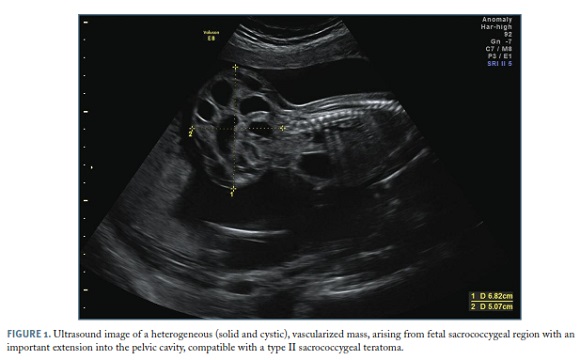

The picture presented here (Figure 1) shows a predominantly cystic mass arising in the fetal sacrococcygeal region, with 68 x 50 mm of major axis, vascularized, and detected at the 20-22 weeks ultrasound examination. The fetus, who had a normal ultrasound examination at 13 weeks, also presented hyperechoic kidneys with dysplastic aspect, a distended bladder and subjectively increased amniotic fluid. Echocardiography showed no anomalies. The couple opted for termination of pregnancy and the histopathological analysis confirmed an immature teratoma with an important extension into the pelvic cavity, causing anterior displacement of the perineum and pelvic organs. There was also hyperplasia of the erythroid lineage in the hepatic sinusoids, probably due to anemia related to the presence of the tumor.

Sacrococcygeal teratoma (SCT) is the most common congenital tumor, with an incidence of 1:40,000 live births. It derives from multipotential embryonic stem cells from the anterior surface of the sacrum or coccyx. The majority of cases are sporadic, although a familiar subtype may be present in 25%1. On ultrasound, SCT presents as a heterogeneous mass of variable size that stands out from the sacrococcygeal region, with dense aspect or acoustic shadowing suggesting calcifications (not perceptible in this image)2. Other ultrasound signs include the presence of alterations caused by compression of adjacent structures, as the bladder distension and dysplastic kidneys evident on this image.

85% of SCT are solid tumors with cystic component, being the remaining purely cystic. In the case described here, the ultrasound characteristics fall into a type II SCT with mixed component. Most fetuses with SCT are hemodynamically stable and surgical correction of the tumor can be performed in the postnatal period. However, in case of rapid tumor growth or arteriovenous shunt, there is a high probability of developing heart failure and intrauterine death1.